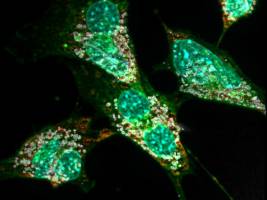

Biowissenschaften - Pharmakologie - 01.09.2020

Forschungsgruppe unter MHH-Leitung findet neuen Therapieansatz durch Behandlung eines Serotonin-Rezeptors Dr. Josephine Labus und Evgeni Ponimaskin im Labor des MHH-Instituts für Neurophysiologie. Auf dem Monitor ist eine Zelle mit dem pathologischen Tau-Protein zu sehen Copyright: Karin Kaiser / MHH Stand: 01.